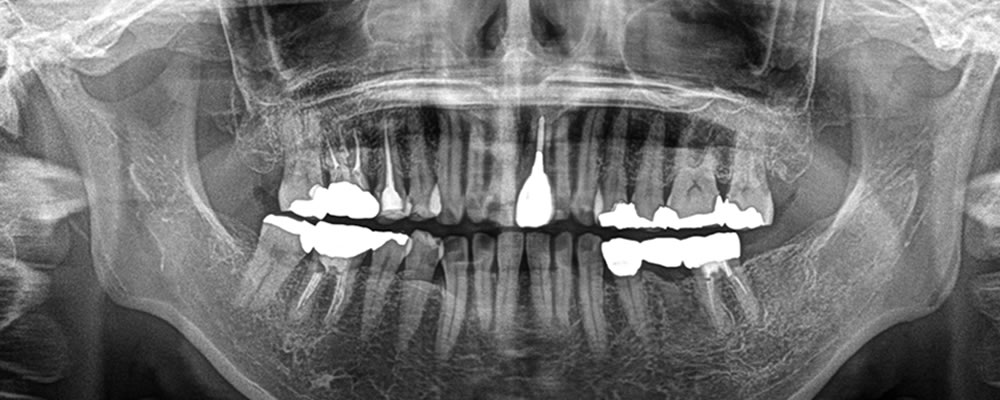

他院で抜歯した部分に実施したインプラント治療の症例

年齢

50代

性別

女性